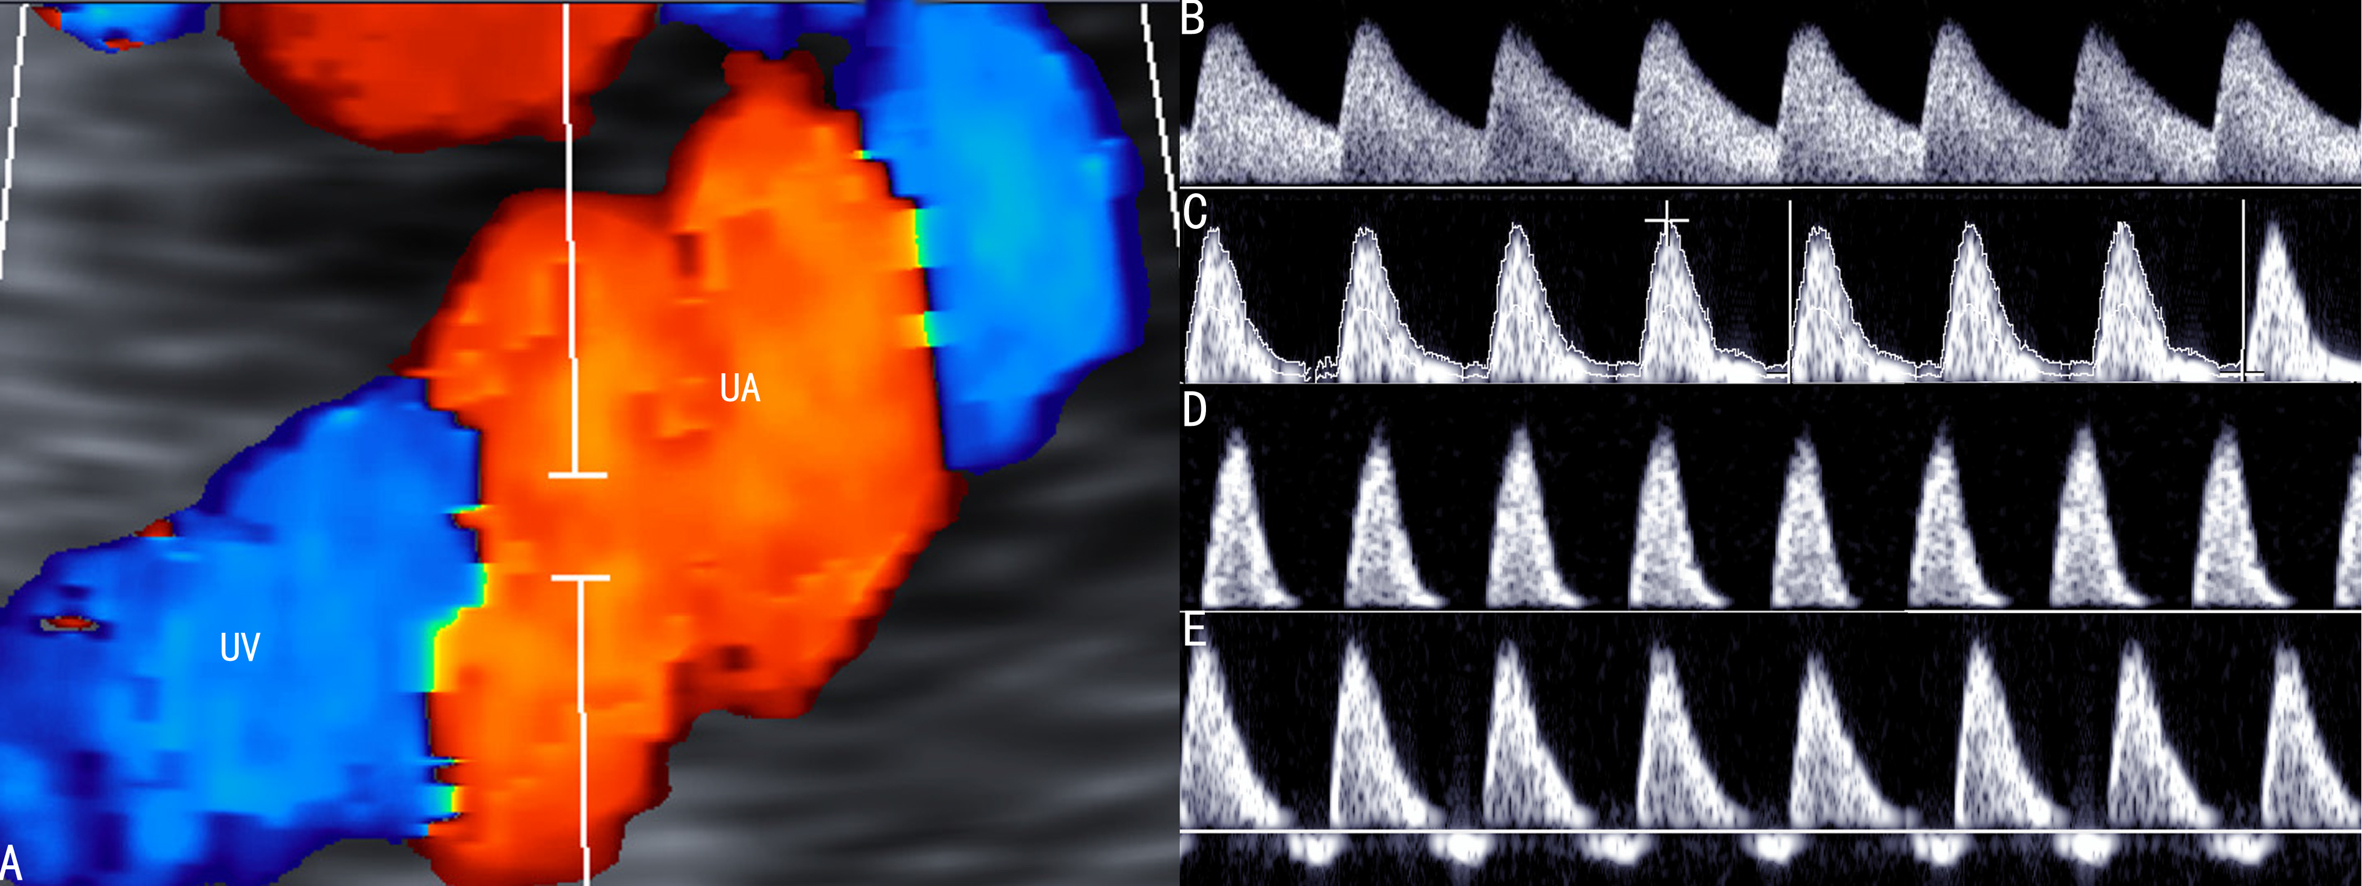

1.FFUA FFUA多普勒超声检查是最常用的FGR评估技术,通过该检查区别FGR的基本原因(图1)。在胎盘功能异常的早期,多普勒超声检查就可以发现FFUA血流阻力增加(图1C),同时,胎盘动脉的血流速度S/D以及PI也相应增加;胎盘功能严重受损时,可以出现舒张期血流消失(图1D),甚至反转(图1E),胎儿出生后围产期死亡率和发病率增加。有报道认为当胎盘三级绒毛血流闭塞超过70%时FFUA舒张期血流出现反向,并伴有严重的FGR(EFW小于3th百分位)和羊水过少。多普勒超声检查发现FUA血流的变化可以提醒临床医生进行早期干预,降低了不良妊娠结局的发生率。

图1 FGR时脐动脉血流速度曲线变化

A:脐动脉CDFI显示

B:正常脐动脉血流速度曲线

C:脐动脉血流速度曲线显示舒张期血流速度降低

D:脐动脉血流速度曲线显示舒张期血流消失

E:脐动脉血流速度曲线显示舒张期血流反向流动